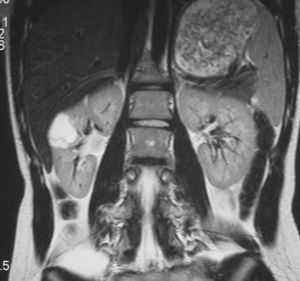

La única paciente con angiomiolipoma renal fue una niña de 10 años con esclerosis tuberosa. En el riñón derecho se identificó una tumoración en el polo superior, con gran crecimiento extrarrenal, densidad homogénea, mayor que la del parénquima renal y menor que la del hígado y relativamente ecogénica (fig. 9). No se constataron áreas grasas, tratándose de un angiomiolipoma con poco componente graso. En el riñón izquierdo se identificaron dos lesiones de pequeño tamaño con atenuación grasa compatibles con angiomiolipomas. Como hallazgos asociados se observaron en el hígado múltiples lesiones con contenido graso de características similares, compatibles con angiomiolipomas intrahepáticos.

Fig. 9. Angiomiolipoma. Niña con esclerosis tuberosa. (A) Ecografía abdominal. Corte renal derecho. Masa renal de ecogenicidad heterogénea y contornos lobulados. (B) Tomografía computarizada abdominal. Masa (M) en riñón derecho. No se identifica componente graso. En el hígado existen tres lesiones de atenuación grasa correspondientes a angiomiolipomas hepáticos (1, 2, 3).